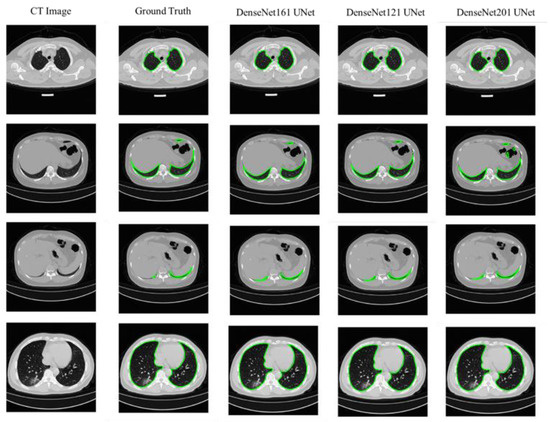

4.1. Lung Segmentation

| Network | Accuracy (%) | IoU (%) | DSC (%) |

|---|---|---|---|

| UNet | 99.70 ± 0.16 | 95.04 ± 0.63 | 96.61 ± 0.52 |

| ResNet18 UNet | 99.70 ± 0.16 | 95.01 ± 0.63 | 96.84 ± 0.5 |

| ResNet50 UNet | 99.70 ± 0.16 | 95.03 ± 0.63 | 96.8 ± 0.51 |

| ResNet152 UNet | 99.70 ± 0.16 | 94.95 ± 0.63 | 96.69 ± 0.52 |

| DenseNet 121 UNet | 99.70 ± 0.16 | 95.35 ± 0.61 | 97.11 ± 0.48 |

| DenseNet 161 UNet | 99.69 ± 0.16 | 95.10 ± 0.62 | 97.19 ± 0.48 |

| DenseNet 201 UNet | 94.88 ± 0.64 | 94.88 ± 0.64 | 97.00 ± 0.49 |

| ResNet18 FPN | 99.65 ± 0.17 | 93.6 ± 0.71 | 95.76 ± 0.58 |

| ResNet50 FPN | 99.65 ± 0.17 | 93.39 ± 0.72 | 95.52 ± 0.6 |

| ResNet152 FPN | 99.66 ± 0.17 | 93.92 ± 0.69 | 96.00 ± 0.57 |

| DenseNet 121 FPN | 99.67 ± 0.16 | 94.53 ± 0.66 | 96.55 ± 0.53 |

| DenseNet 161 FPN | 99.66 ± 0.17 | 94.05 ± 0.68 | 96.11 ± 0.56 |

| DenseNet t201 FPN | 99.67 ± 0.17 | 94.35 ± 0.67 | 96.39 ± 0.54 |